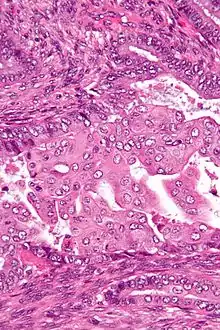

| Micrograph of an atypical polypoid adenomyoma. H&E stain. | |

APAs are characterized by glands with abnormal shapes that: (1) often have squamous metaplasia, and (2) are surrounded by benign smooth muscle.[1] Nuclear atypia, if present, is mild.

The microscopic differential diagnosis includes endometrial carcinoma and endocervical adenocarcinoma.